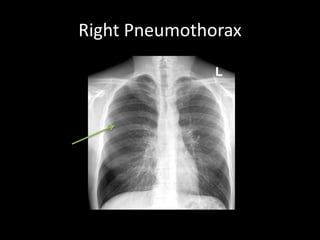

Right Pneumothorax